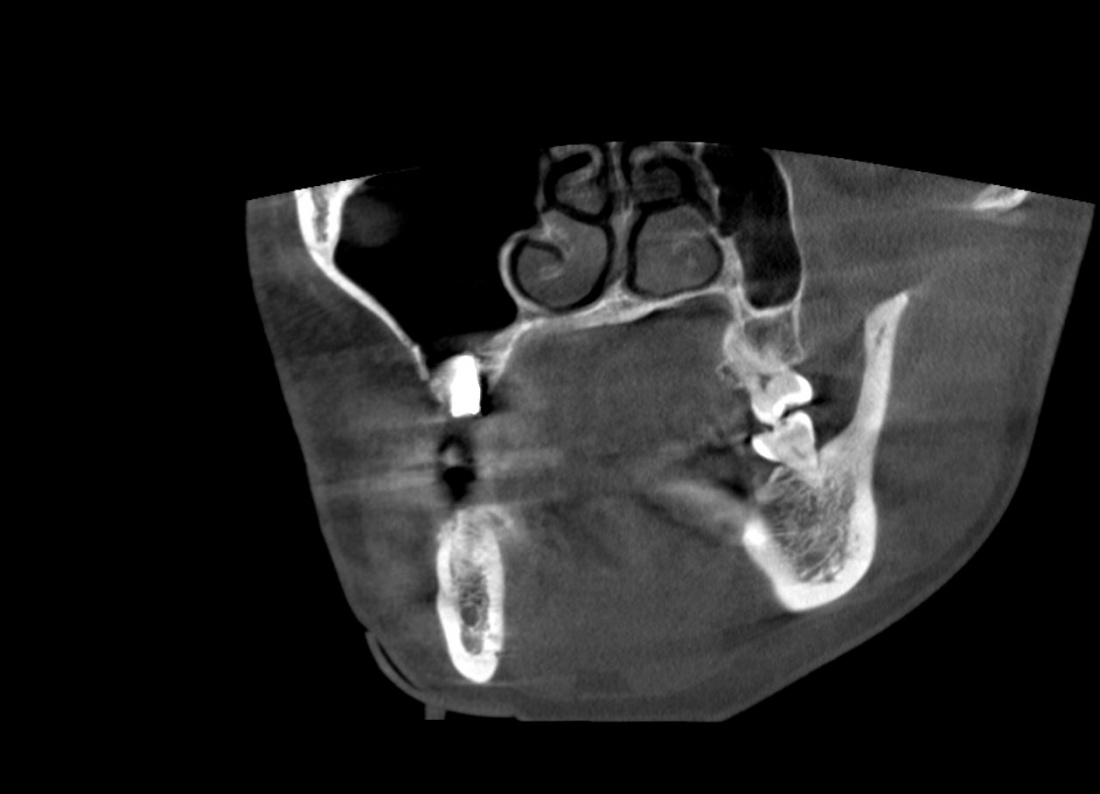

Для этого мы сделали КЛКТ:

И КЛКТ показала нам, что с имплантатами и окружающей костью всё зашибись. Через 12 лет после операции, отсутствия наблюдения, пофигизма в замене временных коронок! Нужны ли тебе еще какие-нибудь доводы в пользу долгосрочной эффективности метода?